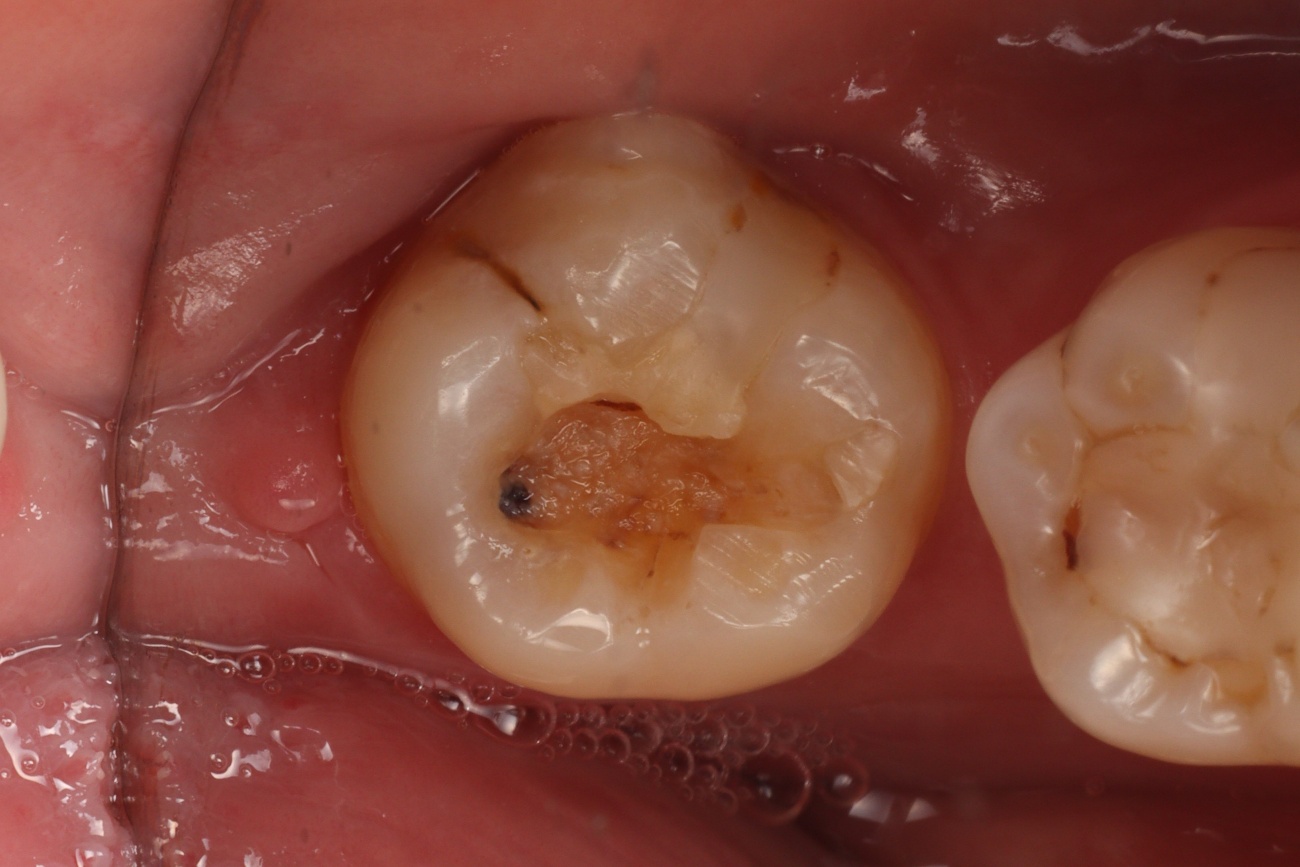

Paciente do sexo feminino, 30 anos, compareceu ao consultório odontológico com queixa de sensibilidade no dente 38, principalmente ao frio e à mastigação. Ao exame clínico, observou-se fratura parcial da restauração em resina composta na face ocluso-palatina do dente, com exposição dentinária central, porém sem sinais de infiltração ativa ou comprometimento estrutural severo (Figura 01).

Figura 1 – Fotografia inicial